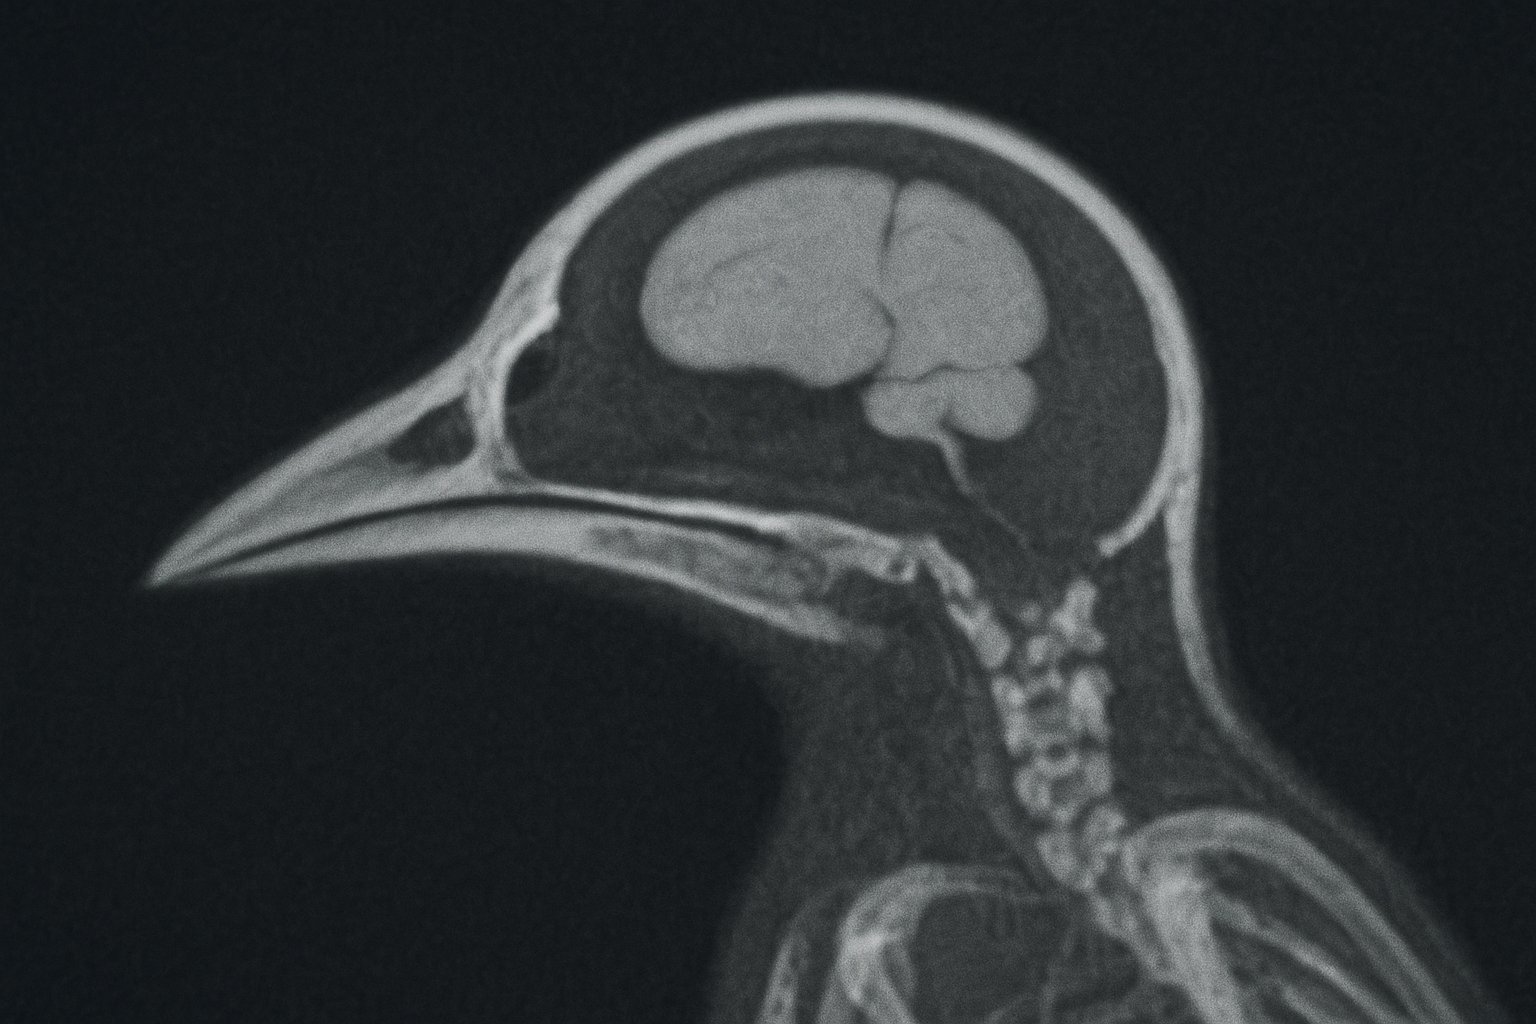

Les oiseaux : un cerveau plus petit à cause des radiations

Une étude menée en 2011 sur 550 oiseaux de 48 espèces a révélé que ceux vivant dans les zones les plus irradiées avaient un cerveau environ 5 % plus petit que la moyenne.

Les oiseaux : un impact comparable à celui des humains

Ces modifications du cerveau sont également observées chez les humains exposés aux radiations, ce qui suggère des effets biologiques universels.